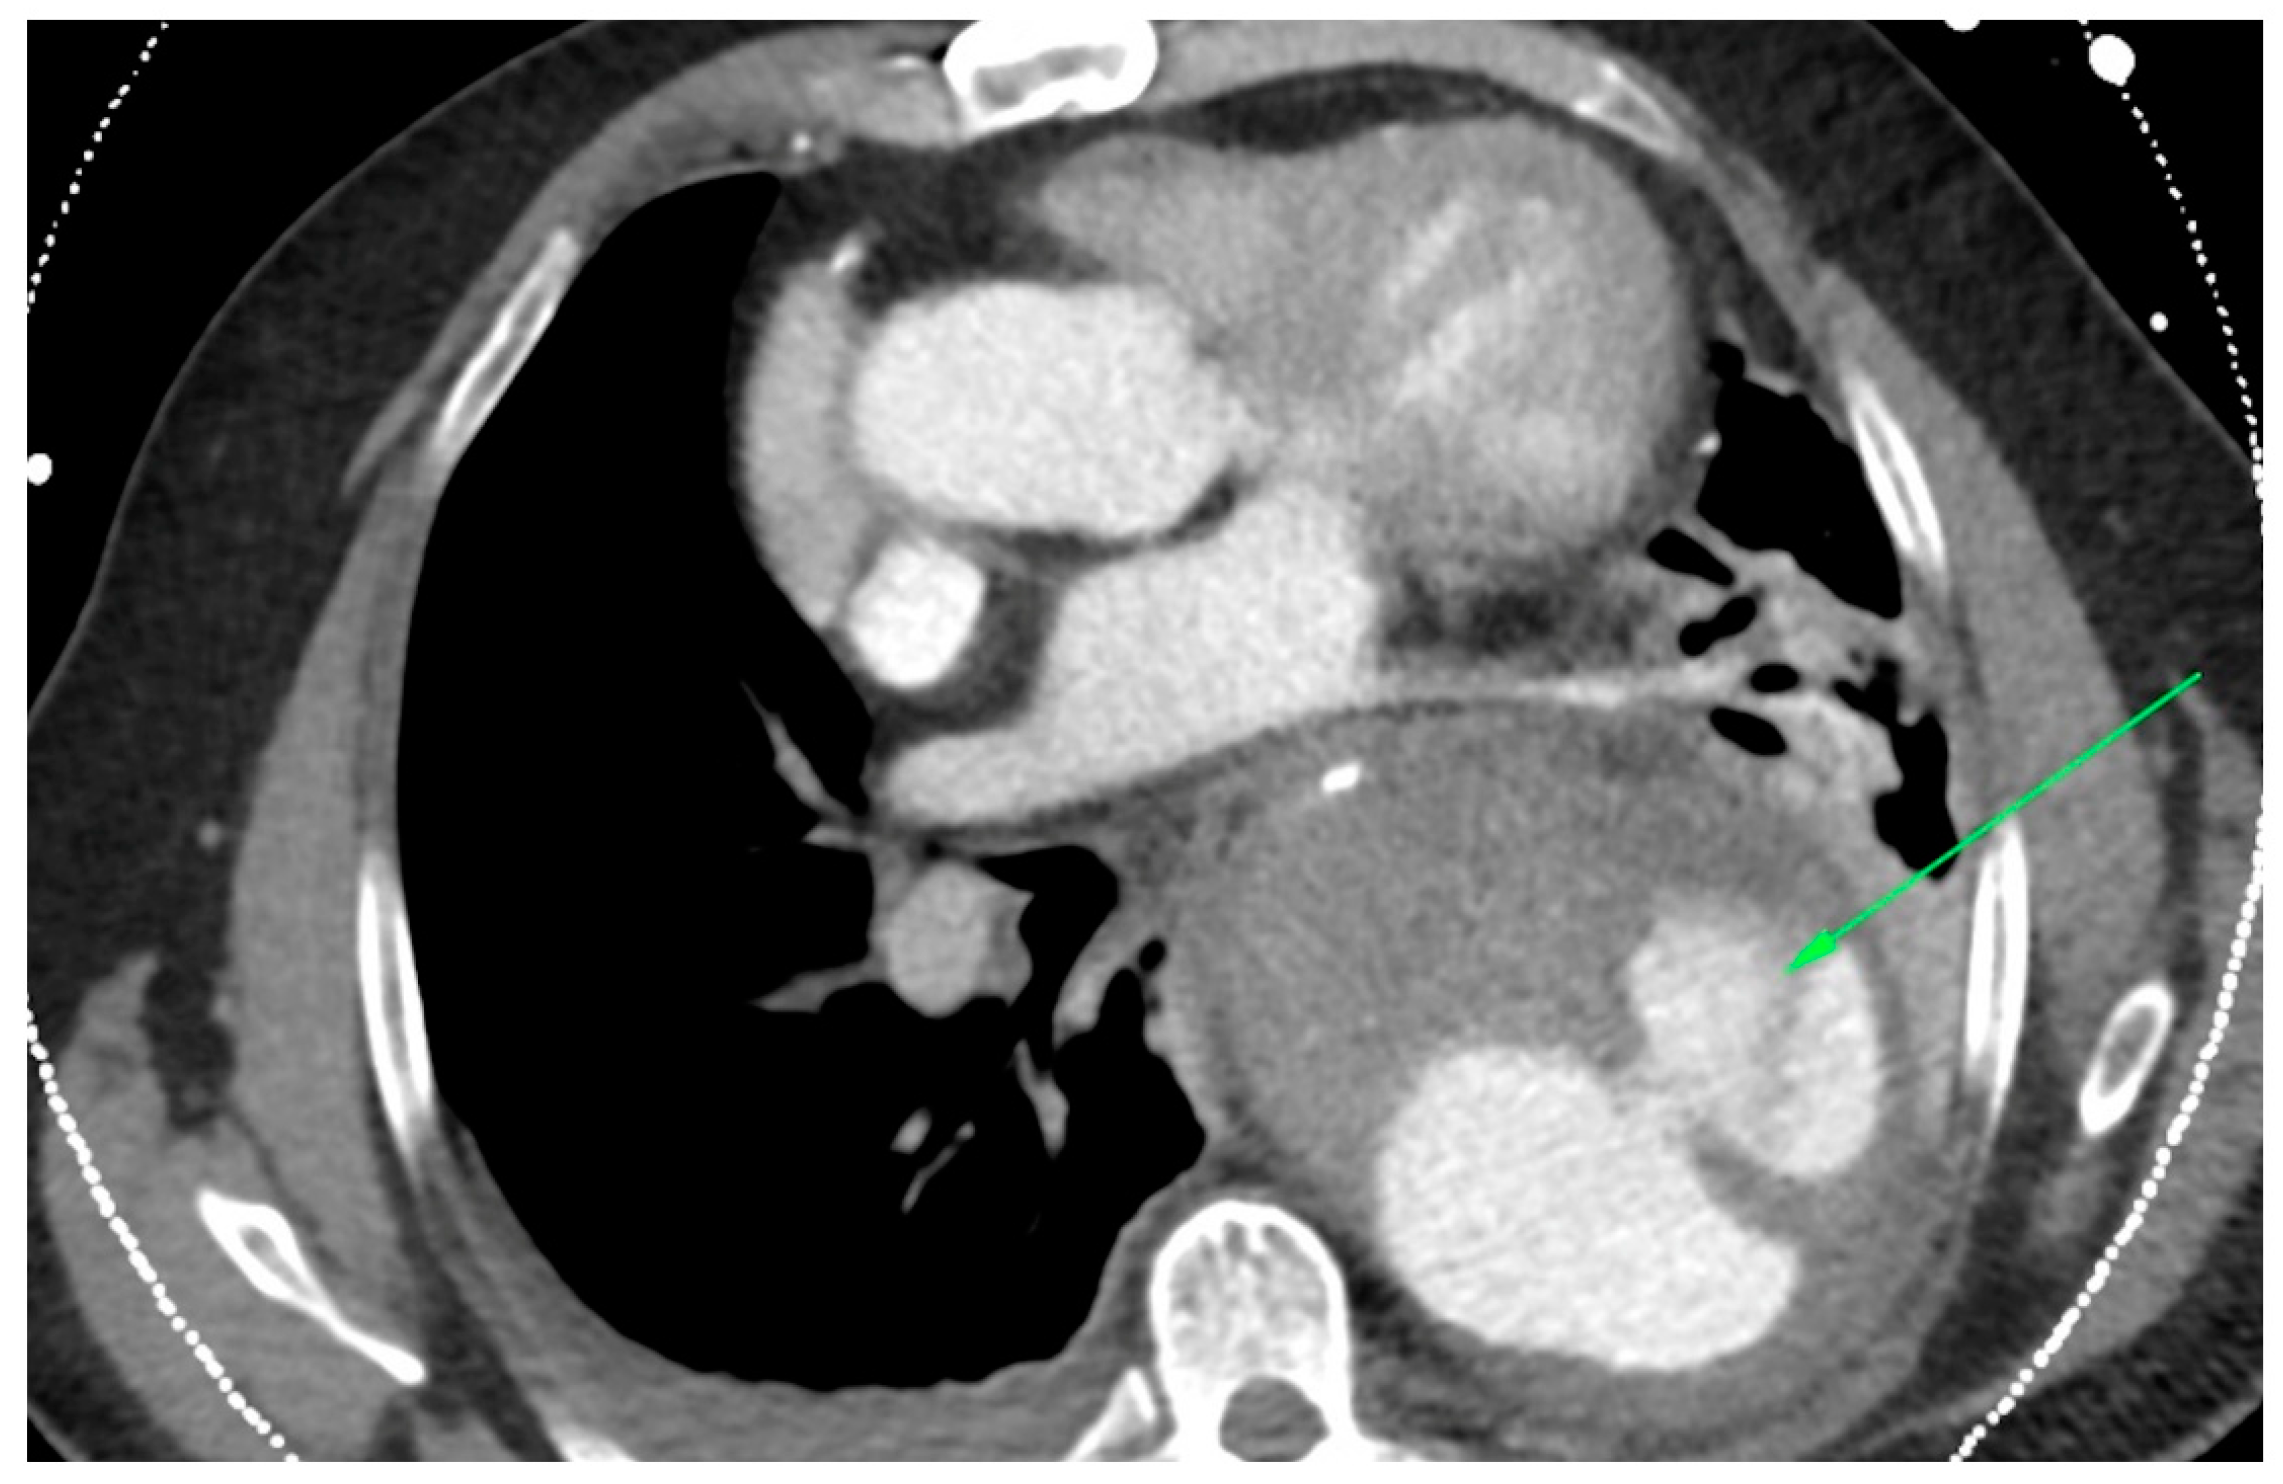

In the primary aortic group, 64% had an aneurysm (Figure 1), 18% had an aortic dissection, and 18% a PAU. In the secondary aortic group, 17% had an iatrogenic aortic lesion after spine surgery, 58% a trauma, and 25% an aortoesophageal fistula (Figure 2 and Figure 3). All patients underwent CT scan for diagnosis and after the surgery (Figure 4). Percutaneous access was performed in 31.8% of the patients in the primary aortic and 41.7% in the secondary aortic group (p = 0.566). An operation in local anesthesia was performed in 31.8% of the patients in the primary aortic group and 25% in the secondary aortic group (p = 0.677). Median duration of hospital stay was longer in the primary aortic group compared to the secondary aortic group (14.5 vs. 8 days, p = 0.746). Simultaneous surgery was similarly frequent in both groups (22.7% vs. 25%, p = 0.881). Procedures included: hepatic artery bypass, aortic arch debranching, surgical treatment of a pelvic fracture, thoracotomy, bowel resection, trepanation, ECMO implantation, and splenectomy.

Figure 1.

CT-scan of a thoracic aortic aneurysm rupture (green arrow).